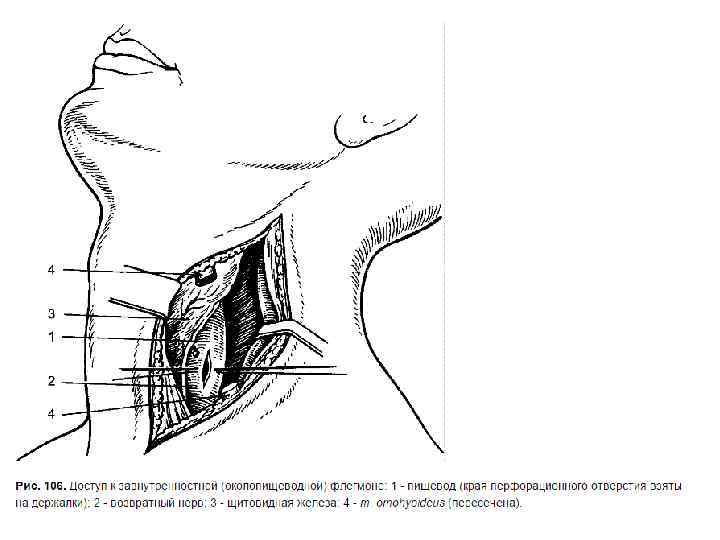

Хирургические доступы к пищеводу • Шейный доступ v Воротникообразный разрез на передней поверхности шеи v Косой разрез Разумовского по переднему краю левой грудиноключично-сосцевидной мышцы • Показания. Удаление инородных тел, глоточнопищеводные дивертикулы, околопищеводные абсцессы и верхнегрудинные медиастиниты.

Хирургические доступы к пищеводу • Шейный доступ v Воротникообразный разрез на передней поверхности шеи v Косой разрез Разумовского по переднему краю левой грудиноключично-сосцевидной мышцы • Показания. Удаление инородных тел, глоточнопищеводные дивертикулы, околопищеводные абсцессы и верхнегрудинные медиастиниты.

• Левую долю щитовидной железы вместе с трахеей и мышцами (грудино-подъязычной, грудинощитовидной) оттягивают и отодвигают кверху и вправо. Перевязывают нижнюю щитовидную артерию, отодвигают кверху лопаточно-подъязычную мышцу (при короткой шее её пересекают). Разъдиняют тупым способом листок внутришейной фасции, обнажают клетчатку пищеводно-трахейной борозды, где проходит левый возвратный гортанный нерв. Стенку пищевода определяют по красному цвету и продольной исчерченности.

• Левую долю щитовидной железы вместе с трахеей и мышцами (грудино-подъязычной, грудинощитовидной) оттягивают и отодвигают кверху и вправо. Перевязывают нижнюю щитовидную артерию, отодвигают кверху лопаточно-подъязычную мышцу (при короткой шее её пересекают). Разъдиняют тупым способом листок внутришейной фасции, обнажают клетчатку пищеводно-трахейной борозды, где проходит левый возвратный гортанный нерв. Стенку пищевода определяют по красному цвету и продольной исчерченности.